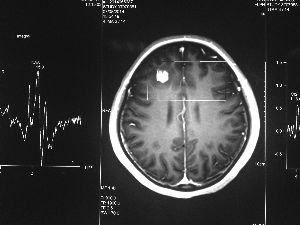

方框亮點為CT片顯示的異物

今年6月份,張敏在宿舍休息時,又發(fā)起了癲癇,也是口吐白沫,渾身抽搐。送到蘇州一家大醫(yī)院,頭顱核磁共振檢查出,張敏大腦右額葉處有一處病灶,也就是大腦額頭處有個東西。

腦袋里的東西,到底是腫瘤還是其他什么東西,這個謎像個石頭一樣,壓得張敏一家人喘不過氣。7月份,張敏一家又來到南京腦科醫(yī)院求醫(yī),第三次檢查后,醫(yī)生覺得很像是寄生蟲。不過,影像的檢查,只能作為醫(yī)生推測的依據(jù),具體是什么,只有手術拿出來后才能知道。